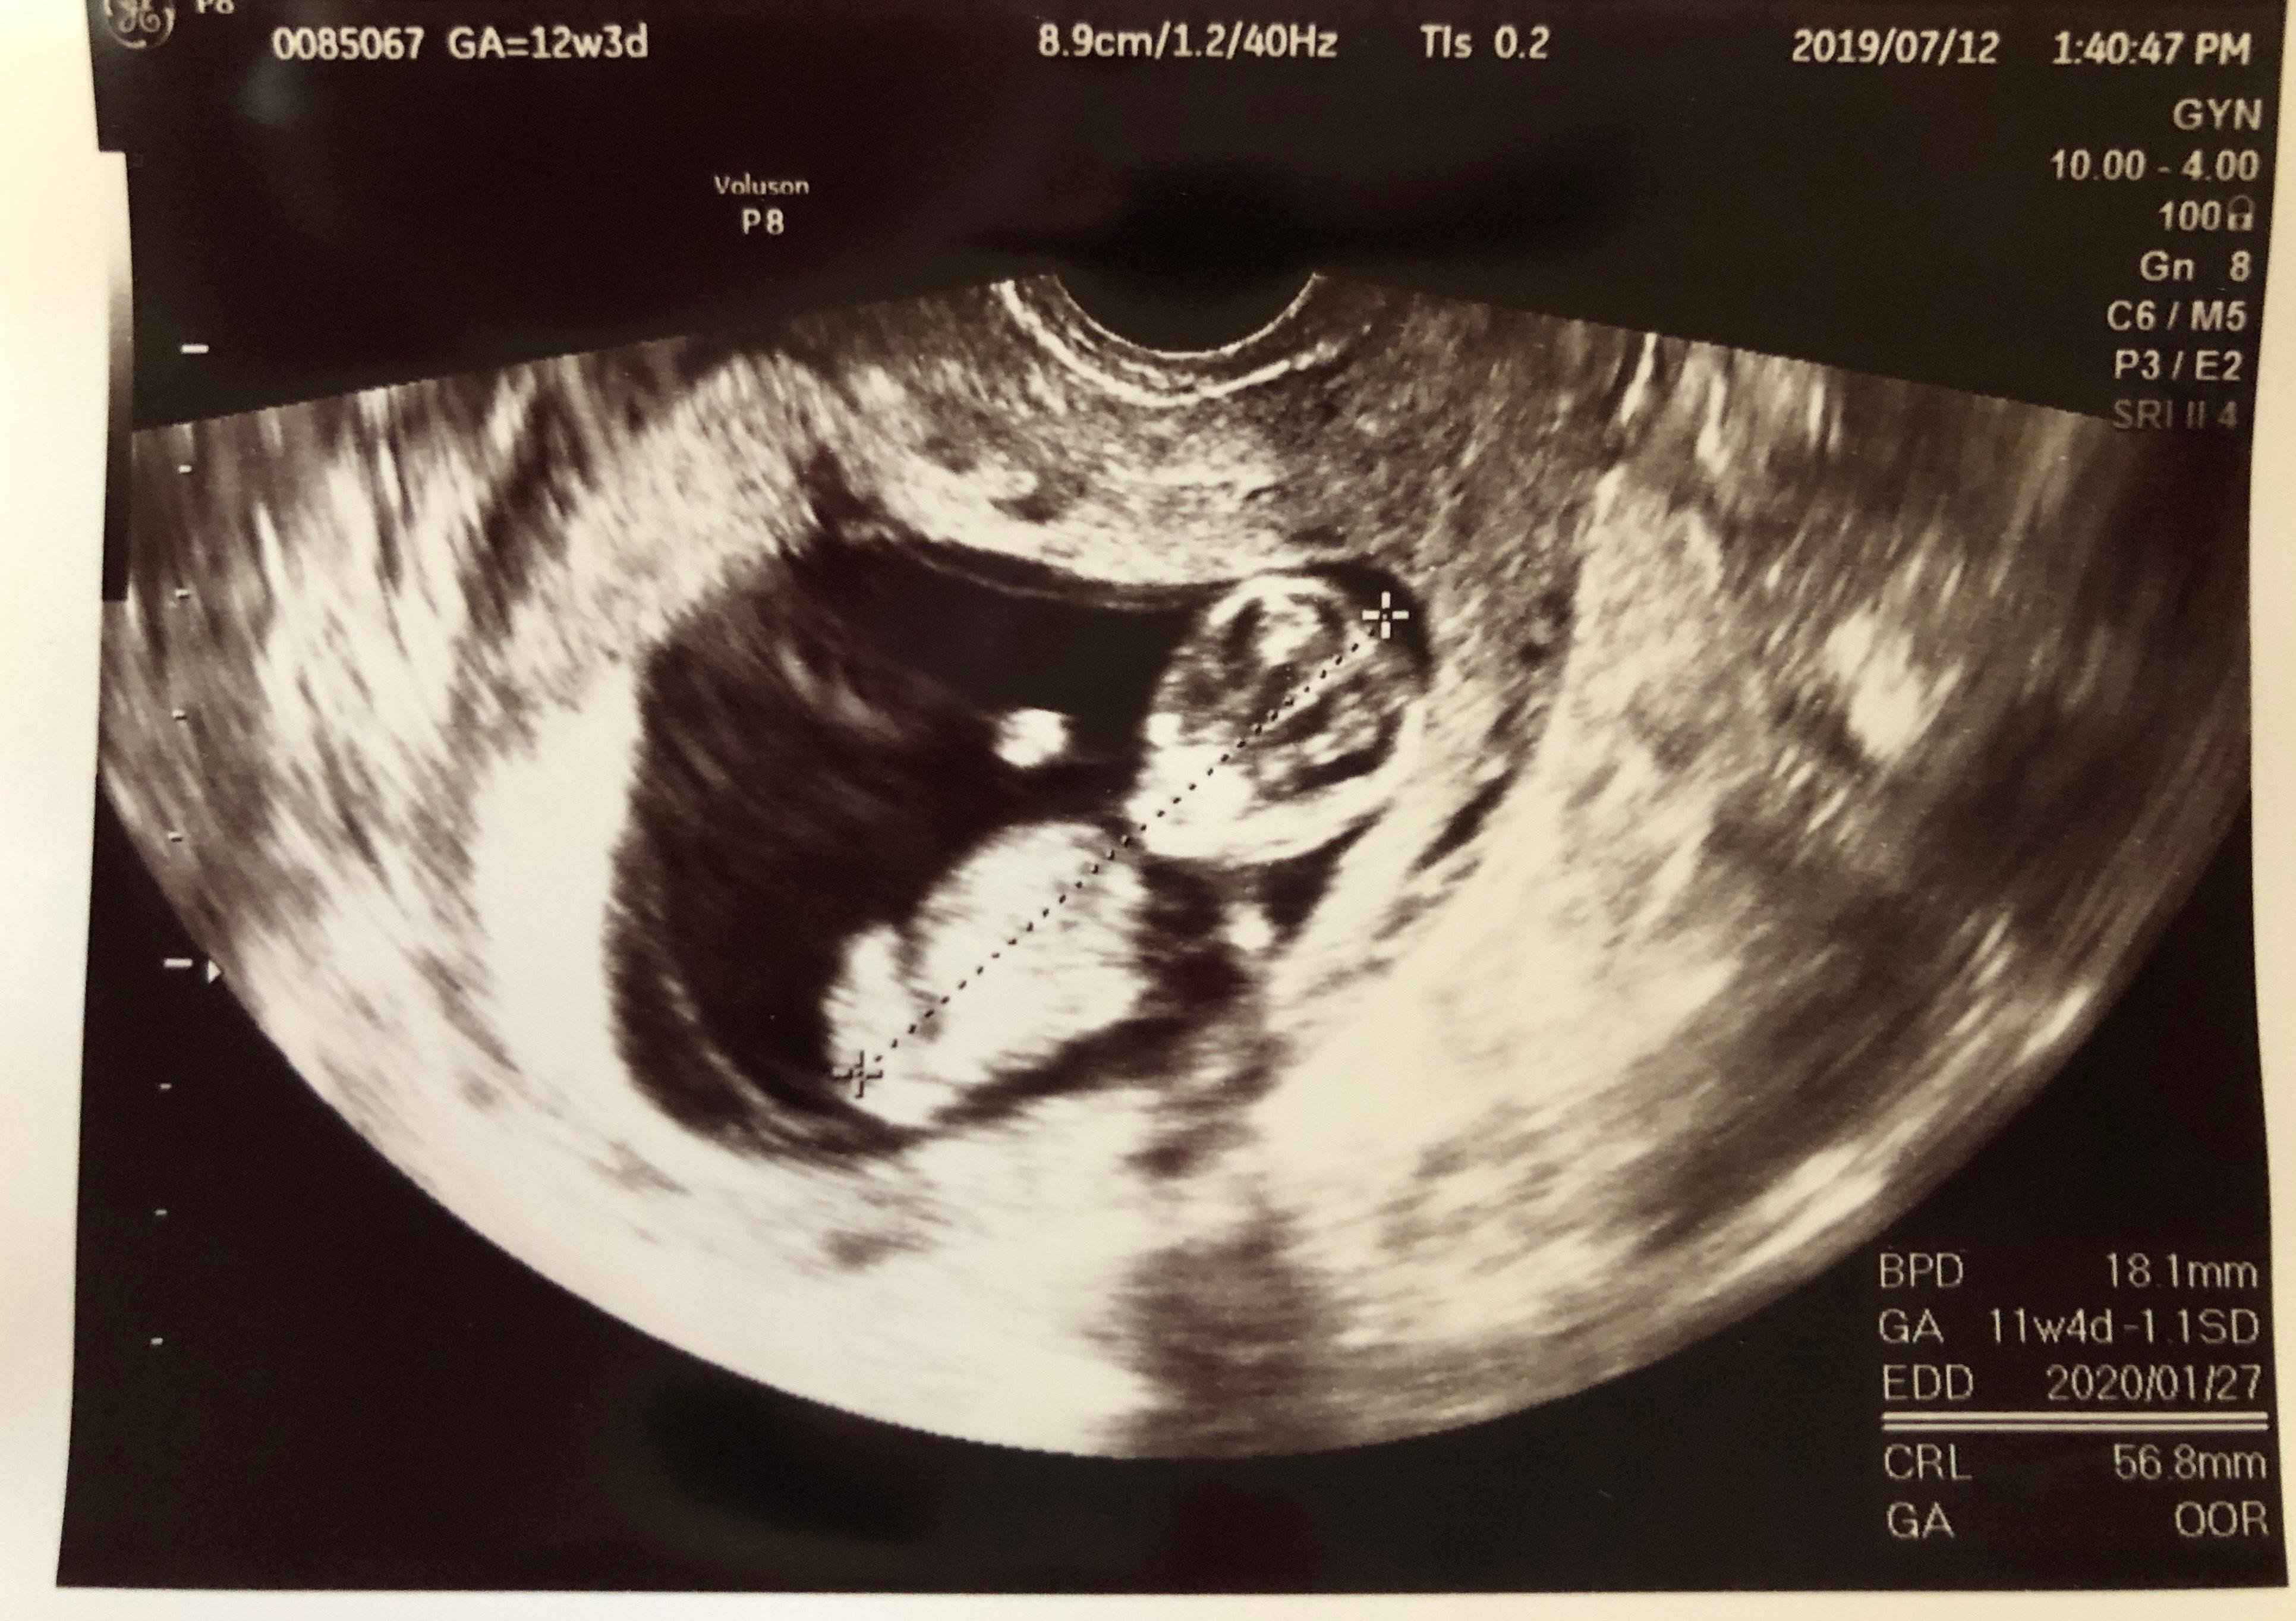

妊娠12週目 つわりで体重減少

妊娠12週での健診。赤ちゃんは両手を挙げて、バンザイポーズを見せてくれました。つわりでだるさと眠気がひどく、長男のお世話で精一杯の毎日。自分のことは後回しになり、体重が6kgも減少してしまいました。健診ではケトン体も出てしまい、先生から注意を受けました。

赤ちゃんはしっかり大きくなってくれていましたが、そこからは自分の食事も気を遣うようになりました。